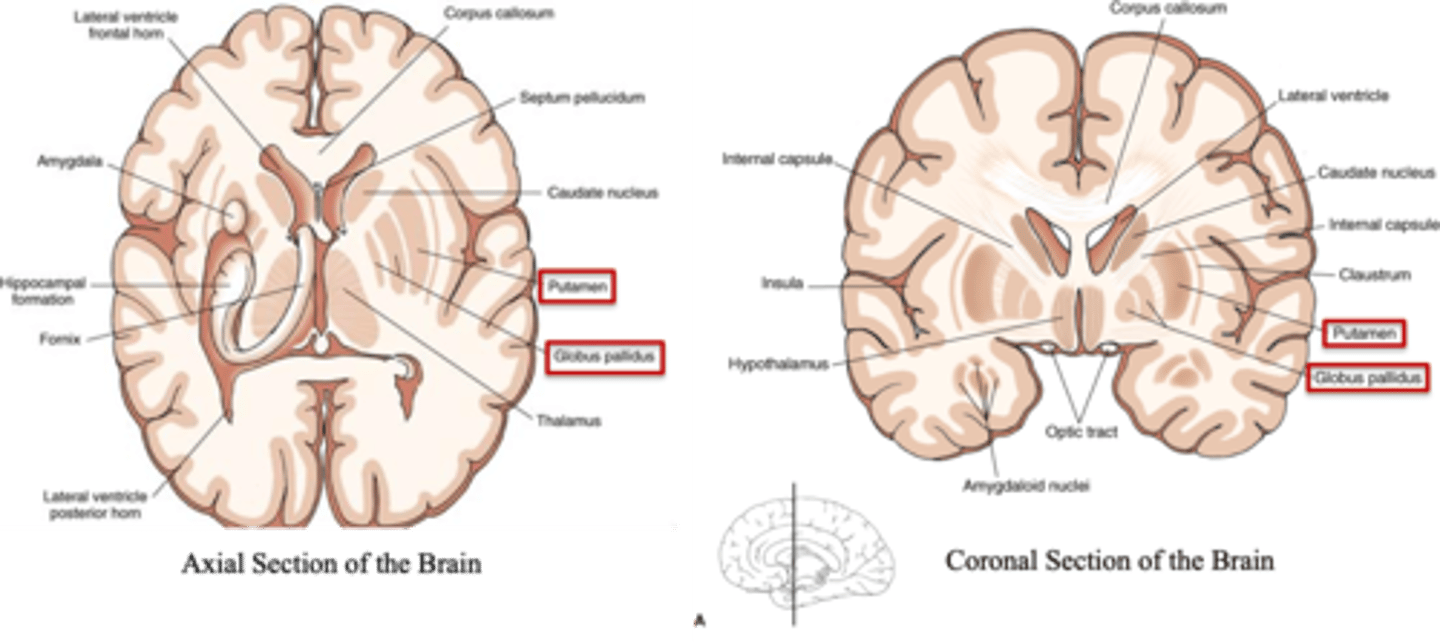

what are the 3 parts of the basal ganglia? what runs between them?

1. caudate nucleus

2. putamen

3. globus pallidus

internal capsule

what part of the basal ganglia is the C-shaped structure that is most medial?

caudate nucleus

what part of the basal ganglia is medial to the putamen?

globus pallidus

the putamen and globus pallidus of the basal ganglia are collectively called the _______________ nucleus

lentiform